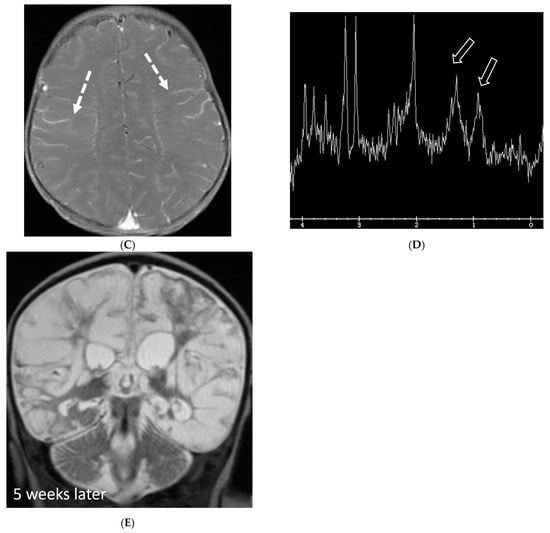

HSV 2 typically causes diffuse cortical involvement with diffusion restriction, loss of gray white matter differentiation and basal ganglia involvement in early stages [98]. HSV 1 typically occurs in older children and adolescents and leads to asymmetric temporal lobe involvement with relative sparing of the basal ganglia (Figure 19).

Figure 19.

17-day-old girl with seizures. Axial T2 (A), axial DWI (B), axial T1 post contrast (C), short TE spectroscopy (D) and coronal T2 (E): There is loss of gray white matter differentiation indicating edema in bilateral frontal lobes (arrows). Extensive ischemic changes involving bilateral frontal, bilateral parietal lobes, bilateral perisylvian regions, bilateral thalami (curved arrows). Extensive LME is identified in the effected regions (dashed arrows). Abnormal elevation of lipid/lactate in both basal ganglia and white matter (open arrows). The above constellation of features are concerning for meningitis/cerebritis. Follow up MRI 5 weeks later demonstrates evolution of extensive ischemic changes into extensive cystic encephalomalacia and gliosis in the supratentorial brain, with ex vacuo enlargement of the ventricular system. CSF analysis: HSV-2.